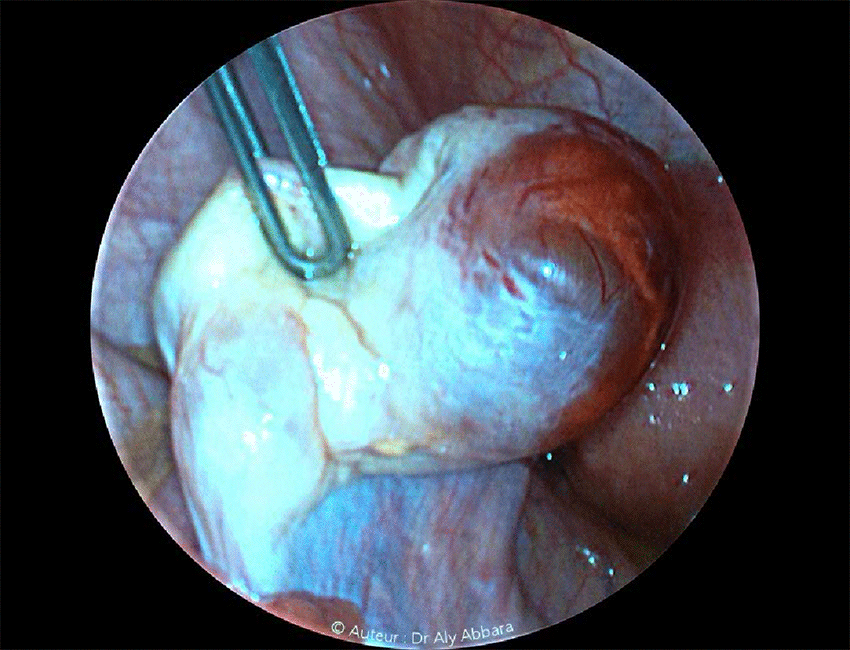

- Cette image clinique montre un ovaire gauche contenant un follicule mature pré-ovulatoire bombant à la surface de l'ovaire et entraînant l'extrême amincissement du cortex ovarien avec un début d'hémorragie sous corticale diffuse témoignant d'une ovulation imminente.